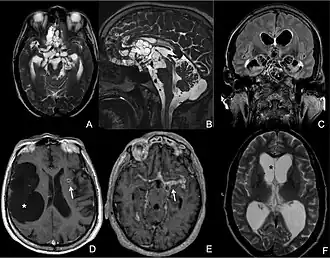

| Magnetic resonance image of a patient with neurocysticercosis demonstrating multiple cysticerci within the brain[1] | |

Neuroimaging

CT scans and magnetic resonance imaging (MRI) give objective information about the number and pattern of lesions, the stage of healing, and how the immune system is responding to the parasites.[19] MRIs are better for evaluating different spatial planes and provides clearer images, which helps in identifying small lesions at the back of the brain or near the skull that may be missed on CT scans. CT scans are more sensitive at detecting calcium buildup in the brain due to its ability detect calcifications in the brain.[30]

Live vesicular cysts are small, round lesions with little swelling around them and do not need contrast for imaging. The tapeworm head (scolex) usually appears as an asymmetric nodule inside the cysts. Multiple live cysts with these heads corroborate the diagnosis. Once the cysts begin to break down (colloid cysts), their borders become unclear, they are surrounded by swelling and exhibit significant ring or nodular contrast enhancement. Calcified cysticerci are shown on CT scans as non-enhancing hyperdense nodules without swelling.[20]